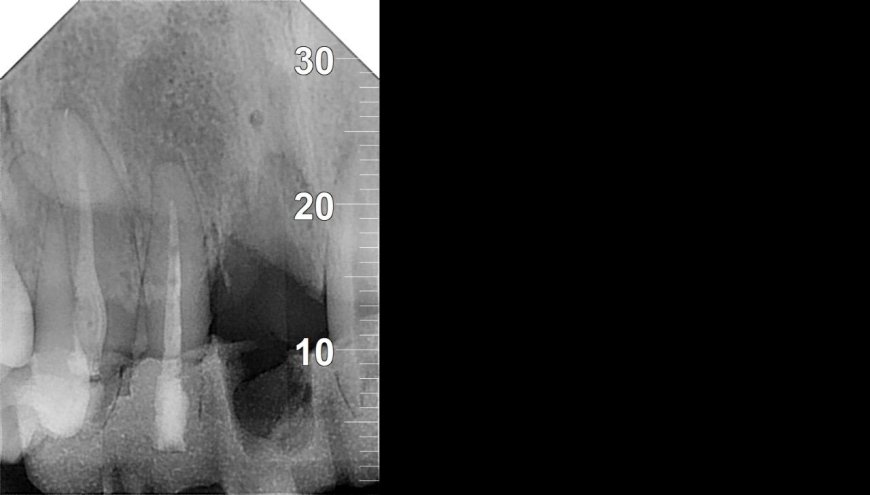

18 الدكتور احمد حسان | أفضل دكتور أسنان في الاردن